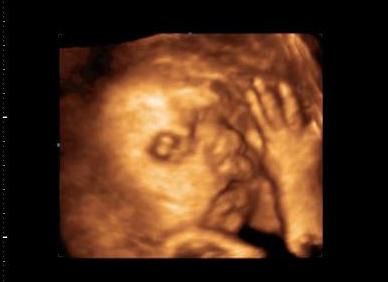

Dalma tegnap az uh-n megmutatta milyen rendes csaj.. Befordult irányba

kaptunk ajándék képet:

Kép